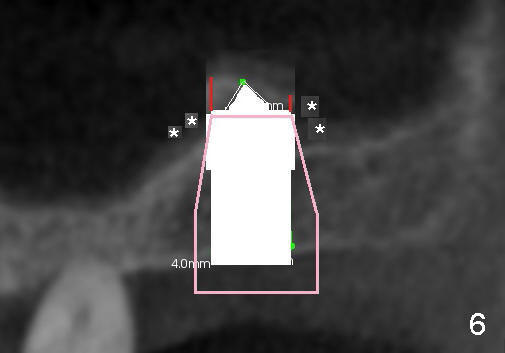

Fig.1 shows the sagittal section of the upper right posterior quadrant (3: #3 palatal root, 2: edentulous area to receive implant; S: sinus). The bone height is 5.8 mm. If the trephine bur with 4 mm outer diameter) does not engage into the bone easily, a 2.0 mm pilot drill is used to create initial osteotomy short of sinus floor (~4 mm deep). Osteotomy is increased by sequentially using 2.5, 3.0, 3.5 and 4.0 mm reamers (Fig.3). Bone shaving is saved. The last 1-2 mm of osteotomy (i.e., sinus floor) is prepared using 4 mm trephine bur (Fig.4 red lines). A flat end osteotome (4 mm in diameter, Bicon comprehensive kit) or tap is used to push the sinus floor upward gently and slowly (Fig.5 arrow). Use a small curet to separate the sinus membrane off the sinus floor lateral to the osteotomy. Put the saved autogenous bone graft back to the osteotomy. Push it upward with Bicon bone condenser. When an implant is placed (Fig.6 pink outline, e.g., 6x11 mm), the top is covered by the vital bone, whereas the side by the harvested bone (*, although the latter loses direct blood supply).